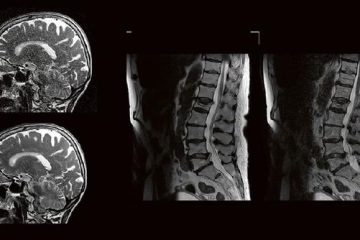

Die technischen Fortschritte bei der Entwicklung neuer Ultraschallgeräte (hochfrequente Ultrabreitband-Linearschallköpfe, Matrixsonden, Verfahren zur Beurteilung der Mikrovaskularisation) sowie Verbesserungen bei der Darstellung von Punktionsnadeln haben in den Gebietender Neurologie, Schmerztherapie, Unfallchirurgie/Orthopädie und Anästhesiologie in den letzten Jahren die Anwendungsbereiche der hochfrequenten Sonographie erheblich erweitert. Unser Anwenderseminar, welches zum 5. Mal ausgerichtet wird, Weiterlesen…